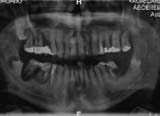

κλινική εικόνα ουλίτιδας περιοδοντίτιδα σε γυναίκα 22 ετών ακτινογραφική εικόνα περιοδοντίτιδας